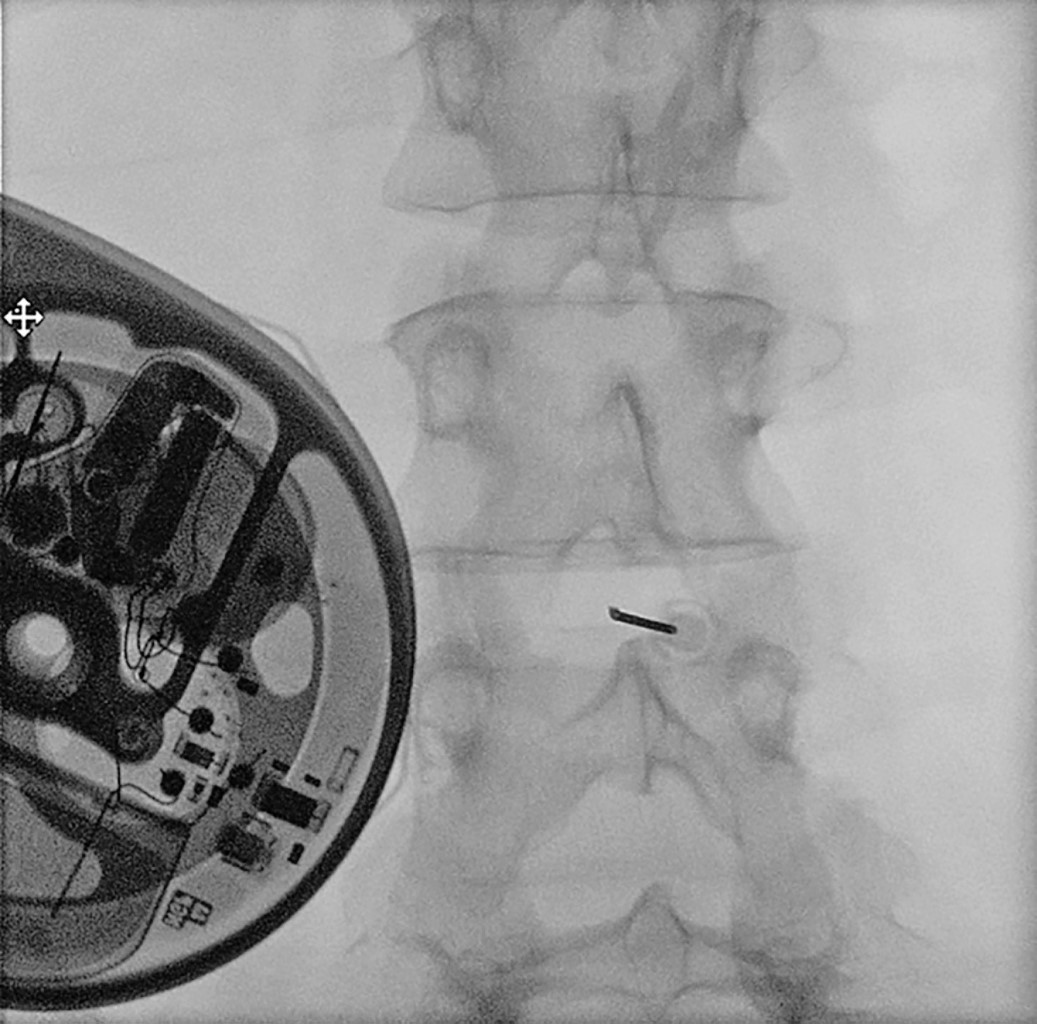

Se realizó una dosis test intratecal con 1 mg de cloruro mórfico, siendo bien tolerado y se decidió implante intratecal definitivo en el mes de noviembre de 2023. Se realizó, en quirófano, bajo condiciones de asepsia y anestesia general, colocación de bomba intratecal efectuando punción dural guiada por fluoroscopía en el espacio intervertebral L2-L3, dejando punta de catéter intratecal a nivel de T7-T8 (Figuras 1 y 2). Se inició la terapia intratecal en modo de perfusión continua con una dosis de 0.6 mg/día de morfina asociado con bupivacaína 1.6 mg/día, sin incidentes.

Figura 1